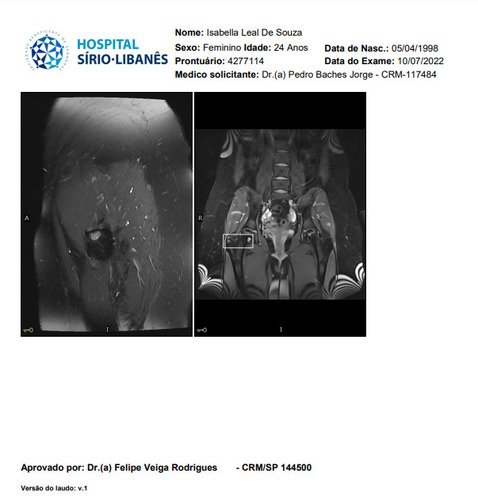

Não sei por onde começar porque e uma história longa e vou tentar resumir, fiquei meses tentando descobrir que eu tinha fibromialgia, porém eu não tenho só isso, tive edemas na coluna, problemas na lombar, e até derrame pleural eu tive, eu pago aluguel que e 1300 mais o condominio que e 450, fora que eu me planejei e não tenho familia pra apoiar entre outras coisas, quando me mudei e planejei pra poder ter o proprio ape eu não sabia que do nada iria ficar doente, em março de 2023 eu pego as chaves mas até la ta dificil, fiz emprestimo e várias outras coisas porque só a medicação de durogesic que eu uso e restiva um a caixa e 650 e o outro 300, podem pesquisar, após um procedimento na lombar cirurgico pra tentar aliviar a dor descobri uma necrose asseptica na cabeça dos dois femur, com risco de ter que colocar uma protese, até pouco tempo estava de muleta, só podia ficar sentada, e mesmo a dor e muito forte, eu ainda não sei a tal outra doença que eu tenho, já aconteceu de eu entrar na emergência e ficar na UTI, tive mais de 10 internações no hospital e não e mentira, minha maior luta e conseguir tratar essa necrose, poder voltar a praticar esportes, sei que tem gente que precisa muito mais mas eu cheguei no meu limite e to até com um aluguel atrasado, todas as coisas que eu estiver pagando eu vou colocar nota fiscal porque eu não to aqui pra fazer ninguém de trouxa, vou colocar exame, fotos de internação entre outras coisas que posso, porque tem algumas que não posso devido porque não quero imagem negativa para local de trabalho (e aonde eu trabalho eles estão me ajudando e muito), e de acordo de como for funcionando a vakinha eu vou vendo se aumento, eu só queria me livrar dessas contas sufocantes primeiro, e agora os médicos estão lutando pra descobrir a outra doença que tenho além dessa da necrose que ta me deixando muito mal e que a fibromialgia atrapalha a descobrir, sei que e chato porque já pedi ajuda 2 vezes, mas conversei com amigos e infelizmente eu não tenho outra opção a não ser pedir ajuda, vou colocar exame de tudo etc, o valor até de emprestimos que estou devendo e tudo mais, e podem me perguntar qualquer coisa que eu respondo e claro, vou postar nota fiscal pra provar que to pagando o que to mostrando, eu to no meu limite, e não e fácil, eu ficava 3 dias seguidos sem conseguir dormir e os médicos não conseguiam descobrir e ainda sigo firme no tratamento porque vou encontrar uma resposta e não posso desistir do tratamento, eu poderia fazer um textao aqui mas com poucas palavras já consigo ser direta, obrigada a quem ajuda e continua me apoiando desde o começo e pra quem não gosta e não acredita e só não ajudar, ninguém vai ficar inventando internações etc pra ficar ai pedindo dinheiro de graça pra ostentar, não gosta só não infernizar, só cada um sabe o sofrimento que ta passando na própria pele e a sua luta diária, agradeço se puder ajudar, aceito tudo que seja positivo e desejo o dobro de bom pra cada um.